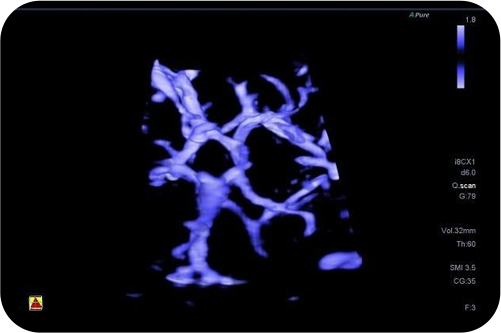

УЗИ система последнего поколения #2

Объемная визуализация микроциркуляции кровяного русла